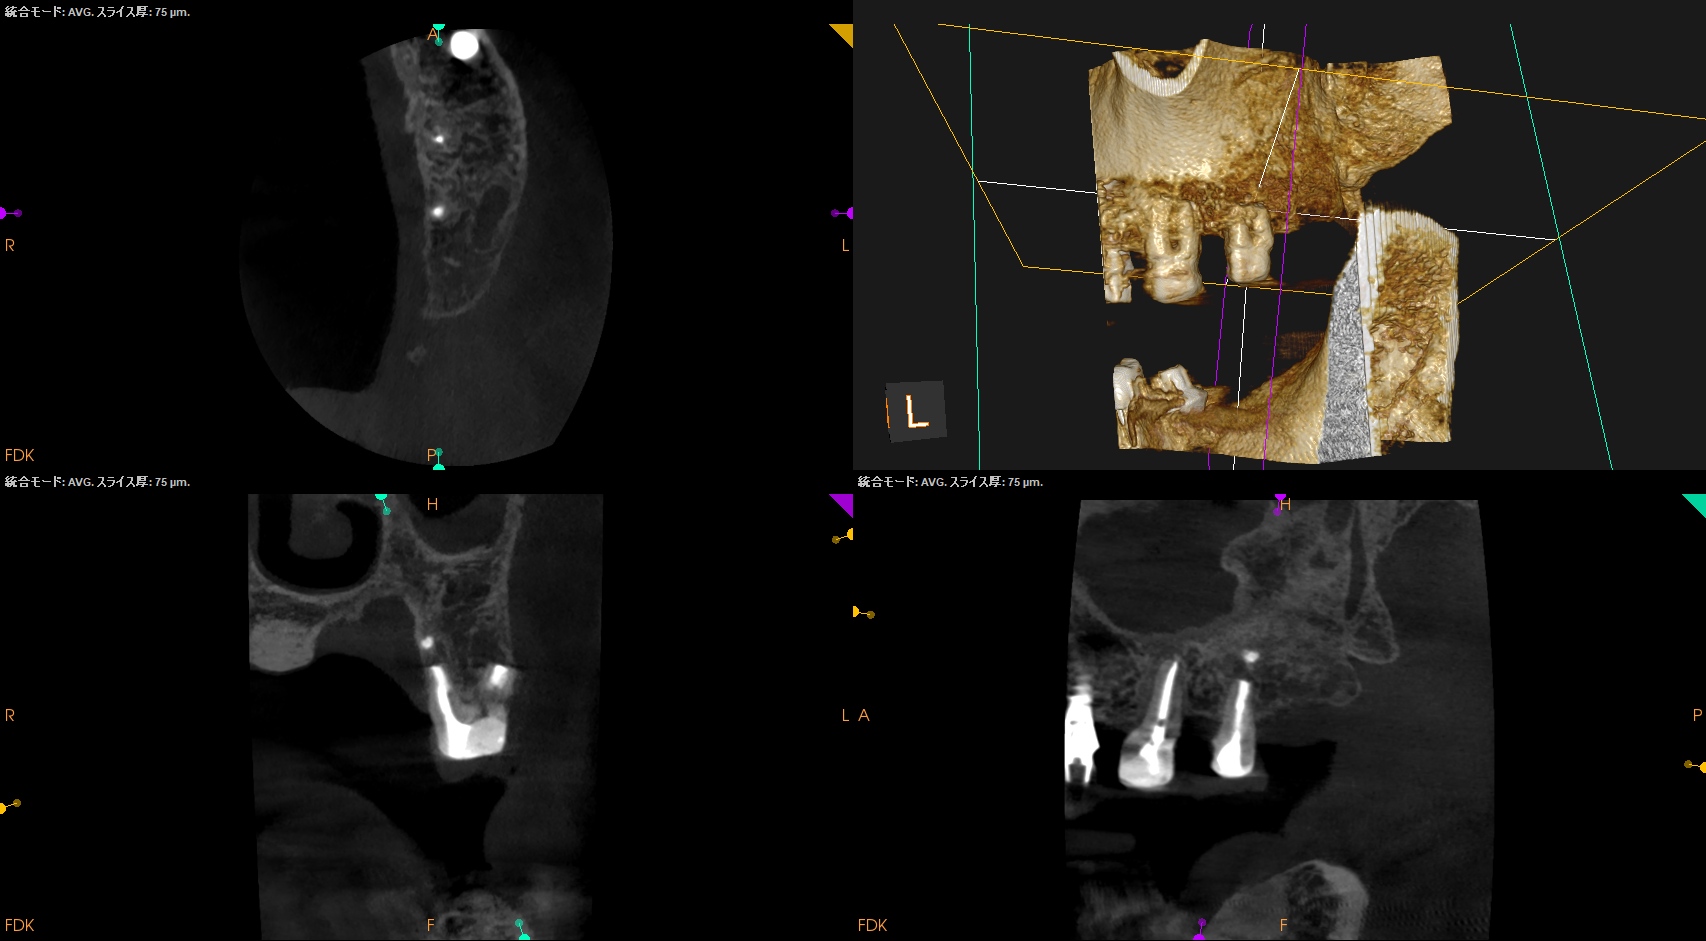

Intentional Replantationから半年が経過した。

治療直後と比較した。

歯槽骨の改善が大幅にみられた。